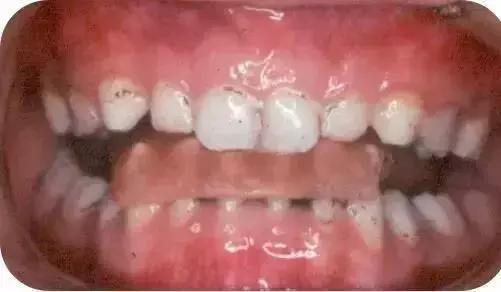

03、上颌颌垫活动矫治器

简单点说,就是喊你把这个上颌颌垫活动矫治器戴到起。

04、下颌斜面导板矫治器

还是简单点说,喊你把这个下颌斜面导板矫治器戴到起。你是不是要问“那跟上面那个有啥不同嘛”?回答:因为娃娃的患病情况不同嘛!